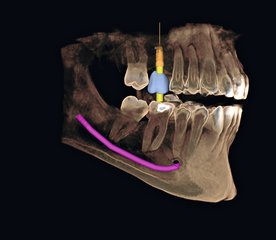

Depuis quelques années, certains nouveaux dispositifs d’imagerie donnent accès, dans de bonnes conditions et à moindre irradiation que le scanner traditionnel, à cette fameuse 3è dimension : on parle de Cone Beam.

Le Cone Beam est bien évidemment utilisé en implantologie dentaire, mais aussi en dentisterie traditionnelle.

- implantologie dentaire